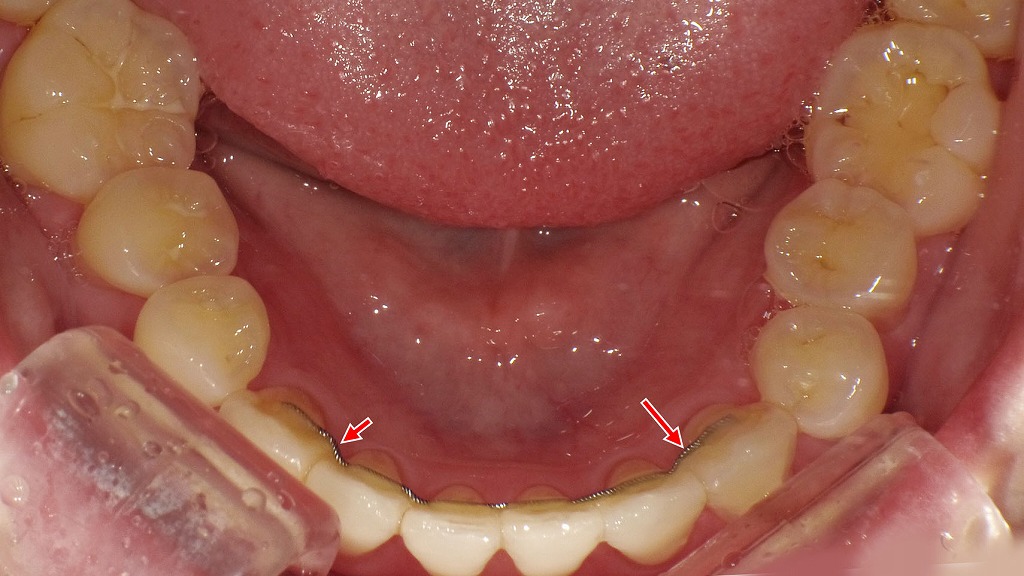

🛡 保定装置(リテーナー)と後戻り防止の重要性

- 種類:

・透明タイプ(マウスピース型)

・ワイヤー固定型(前歯の裏側)

・プレート型(着脱可能) - 装着期間の目安:

治療期間が2年なら、保定も2〜3年が目安。

就寝時のみの装着になることが多いですが、初期は日中も装着します。 - 装着を怠ると?

数ヶ月で歯が戻ってしまい、再治療が必要になるリスクがあります。

❓ 後戻りはありますか?リテーナーは必要?

はい、リテーナー(保定装置)は必須です。

矯正が終わっても、歯は元の位置に戻ろうとする「後戻り」の性質があります。

🔄 リテーナーの種類

- マウスピース型(透明で目立ちにくい)

- ワイヤー固定型(前歯の裏側に設置)

📌 装着時間は最初の数ヶ月は20時間以上 → 徐々に就寝時のみへと移行します。